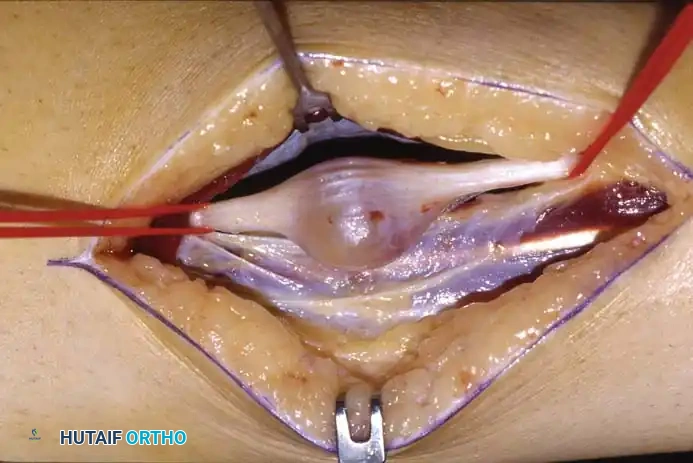

Fig 4: Gross unsectioned specimen of a neurilemoma excised from the tarsal tunnel.

Fig 5: Intraoperative view and sectioned gross specimen. Note that while neurilemomas are nerve sheath tumors, they are intimately involved with the fascicles. Excision requires meticulous microsurgical dissection, and occasionally, a small non-functional nerve branch must be sacrificed to achieve complete removal.

If a space-occupying lesion such as a neurilemoma or ganglion is encountered, it must be carefully dissected free from the epineurium. Use microsurgical techniques to separate tumor capsules from functional nerve fascicles.